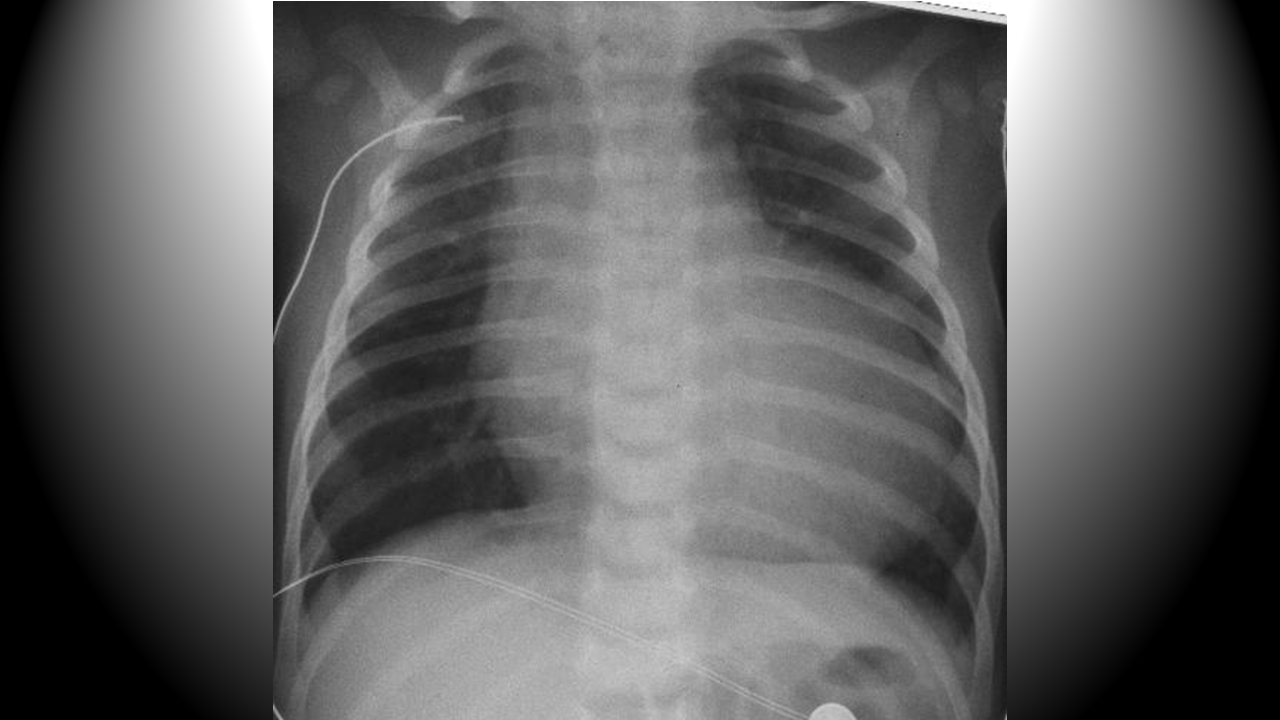

Someone with a cough and fever may simply have a viral illness, or he may have pneumonia. Our obligation is to evaluate for the pneumonia. It’s ok if we “miss” the diagnosis of a cold. It could be bad if we don’t recognize the pneumonia.

Reliably elevated in myocarditis, and may help to distinguish this from pericarditis (in addition to echocardiography)

Other causes of elevated troponin in children include: strenuous activity, status epilepticus, toxins, sepsis, myocardial infarction (in children with congenital anomalies). Less common causes of troponemia are: Kawasaki disease, pediatric stroke, or neuromuscular disease.